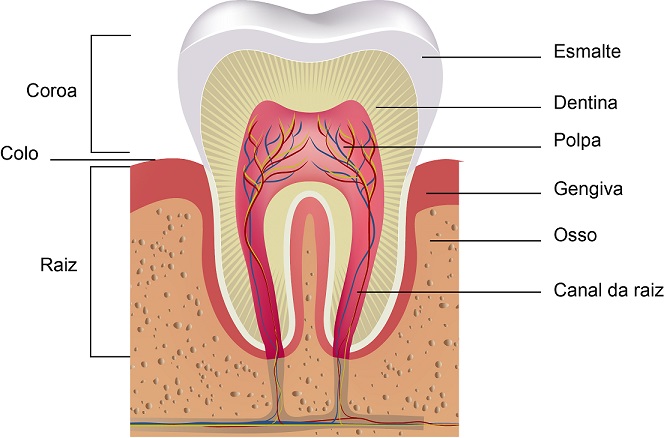

Como acontece a formação de cálculo dental (tártaro)?

O cálculo dental, mais conhecido como tártaro dental, pode ser definido como o acúmulo de um complexo de bactérias calcificado na superfície dental. Essas bactérias já existem normalmente na boca, mas em número reduzido e em sua forma livre, ou seja, não aderidas à nenhuma superfície.

Quando não higienizamos os dentes de forma correta, ocorre um acúmulo de bactérias na superfície dental, inicialmente sem nenhuma calcificação. Esse acúmulo de alimentos e bactérias, forma uma película aveludada nos dentes, chamada de matéria alba. A matéria alba é facilmente removida com uma boa escovação e com o uso do fio dental, mas caso o paciente não consiga removê-la, começa a modificar sua estrutura se tornando cada vez mais complexa e progressivamente calcificando. No momento em que se forma a calcificação, a remoção do cálculo só poderá ser feita em consultório odontológico, através do uso de curetas e/ou de equipamento ultrassônico. O cálculo “novo” tem coloração amarelada clara enquanto o cálculo “antigo” é mais escuro. Esse escurecimento ocorre porque o cálculo é exposto constantemente ao sangue da gengiva inflamada. Na maioria das vezes esse sangramento é imperceptível para o paciente, uma vez que ocorre de forma contínua e crônica.

Quais as consequências do Cálculo dental?

Como já vimos, o cálculo é um acúmulo de bactérias na superfície dental. Esse complexo calcificado pode causar cáries, gengivite, retração gengival, morte pulpar, fístulas, abscessos e até perda óssea (podendo levar à mobilidade parcial ou completa dos dentes).

A exposição radicular causada pela retração gengival leva à dor, sensibilidade ao quente/frio e à perda do cemento que protege a estrutura da raiz dental. Nesses casos, está indicado o recobrimento radicular, seja utilizando resinas compostas, ou com cirurgias de recobrimento radicular. Como esse é um assunto complexo, vamos abordá-lo melhor num próximo post!

Outra consequência muito importante do cálculo dental, são as lesões endoperio. Essas lesões se formam a partir do cálculo dental, ganham a raiz e reabsorvem o osso até chegarem ao ápice radicular causando um problema endodôntico. Podem evoluir para a formação de abscessos e fístulas com drenagem de pus para cavidade oral. Nesses casos, o tratamento é multidisciplinar, necessitando de raspagem radicular e tratamento endodôntico (tratamento de canal).